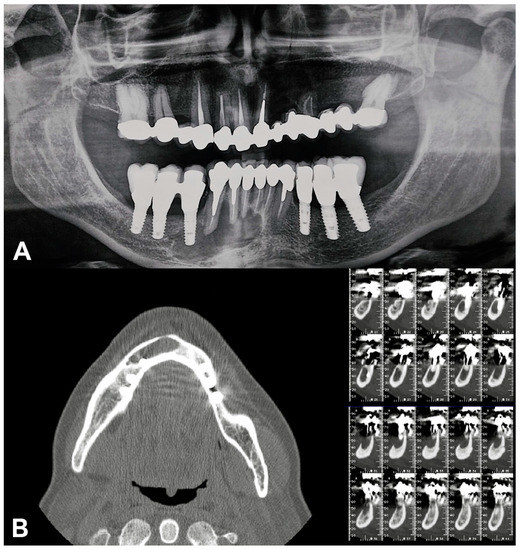

- Implant-supported prostheses from 3.4 to 3.6 and from 4.4 to 4.6.

- Prosthetic rehabilitation on dental support from 3.3 to 4.3. Metallic endocanalar posts in 3.3, 4.2, and 4.3.

- Endodontic treatment on 3.1, 3.2, 3.3, 4.1, 4.2, and 4.3.